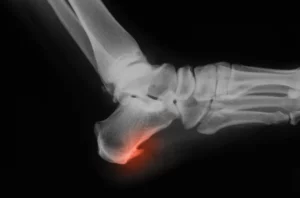

- عکسبرداری با اشعه ایکس

- اندازهگیری زاویه استخوان پا